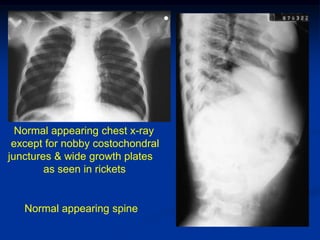

Case #1     Jansen’s Type Metaphyseal Dysplasia

Young boy with short limbs with wide growth plates like rickets

Normal appearing chest x-ray

except for nobby costochondral

junctures & wide growth plates

as seen in rickets

Normal appearing spine